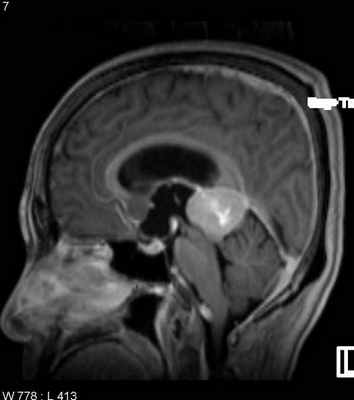

При МРТ головного мозга выявляется образование с широким основанием. Гиперостоз, часто видимый при КТ и на рентгенограммах, при МРТ головного мозга выглядит как утолщение внутренней костной пластинки свода черепа. Кальцинаты, обнаруживаемые при КТ в 20% наблюдений, при МРТ не видны. Опухоль при МРТ довольно однородная по структуре. Прорастание костей свода черепа видно отчетливо как участок повышенного сигнала на МРТ головного мозга любого типа в резко гипоинтенсивной кости. Сигнал от опухолевого узла на Т2-зависимых МРТ зависит от гистологического подтипа: относительно низкой интенсивности (между белым и серым веществом) при фибробластном и высокой при ангиобластном и синтициальном. Отек выражен в различной степени в каждом конкретном случае. Ряд МРТ признаков очень характерен для менингиомы: полоса ликвора между опухолью и тканью мозга, смещение окружающих сосудов. Они отражают неинвазивный характер роста. Смещенную и вовлеченную твердую мозговую оболочку иногда удается визуализировать при МРТ после введения гадолиния, особенно на корональных МРТ срезах. Усиление сигнала при МРТ с контрастированием от оболочки над опухолью с распространением в стороны (симптом “хвоста”) не абсолютно специфично и встречается при МРТ как при менингиоме, так и при лептоменингиальных метастазах. Однако при глиальных опухолях и невриноме при МРТ оно не описано. При обследовании пациентов методом МРТ в СПб с менингиомами серпа (фалькс-менингиомы) и намёта мозжечка рекомендуется делать МР-венографию для определения компрессии синуса и его проходимости. В наших центрах это обязательное исследование перед операцией. На открытом МРТ венография также легко выполнима. Не все центры МРТ СПб придерживаются этой методики.

МРТ головного мозга. Субфронтальная менингиома. Сагиттальная Т2-взвешенная МРТ.